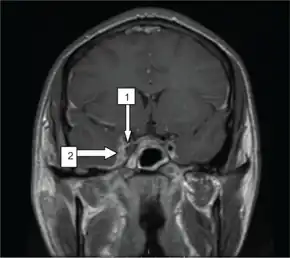

| Oblique section through the cavernous sinus. | |

Sinus films are helpful in the diagnosis of sphenoid sinusitis. Opacification, sclerosis, and air-fluid levels are typical findings. Contrast-enhanced CT scan may reveal underlying sinusitis, thickening of the superior ophthalmic vein, and irregular filling defects within the cavernous sinus; however, findings may be normal early in the disease course. An MRI using flow parameters and an MR venogram are more sensitive than a CT scan and are the imaging studies of choice to diagnose cavernous sinus thrombosis. Findings may include deformity of the internal carotid artery within the cavernous sinus, and an obvious signal hyperintensity within thrombosed vascular sinuses on all pulse sequences.Cerebral angiography can be performed, but it is invasive and not very sensitive. Orbital venography is difficult to perform, but it is excellent in diagnosing occlusion of the cavernous sinus.[12]